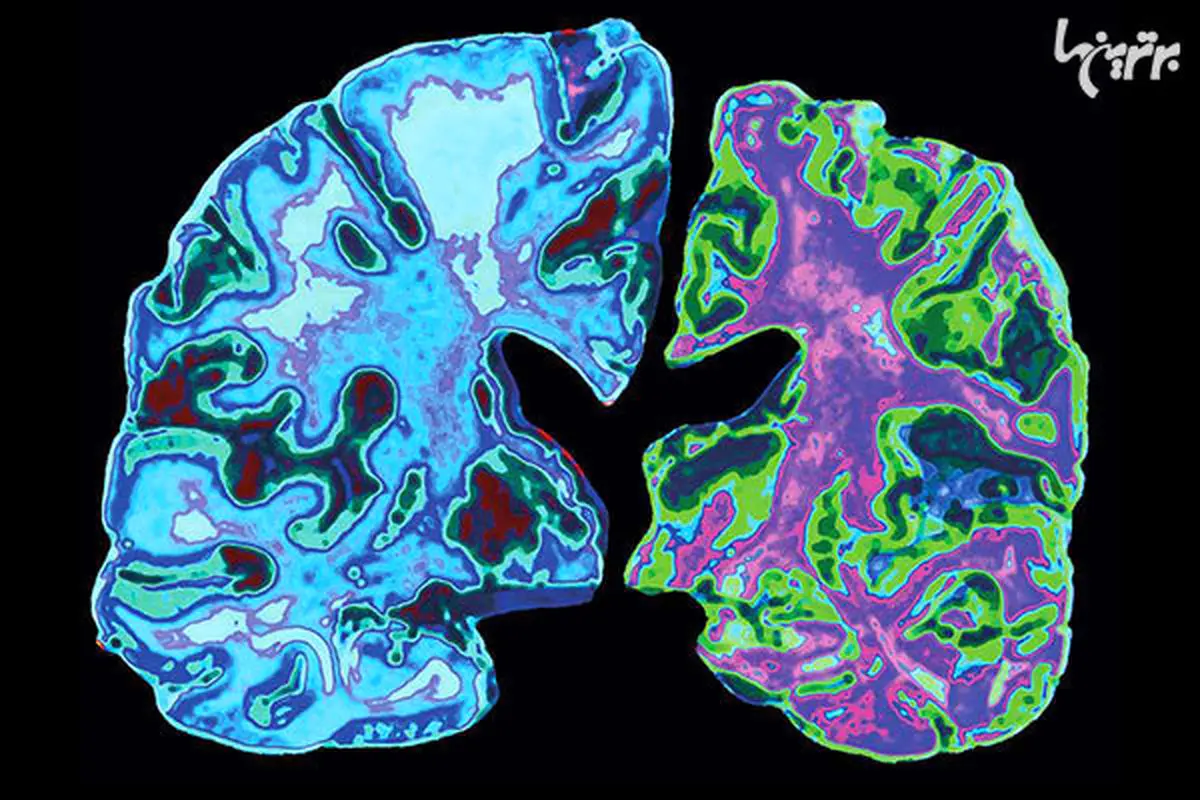

آلزایمر نوعی بیماری عصبیست که پروسه‌ی آرامی دارد و طی آن ارتباط بین سلول‌های مغز تخریب میشود. این بیماری رایج‌ترین نوع فراموشیست. متاسفانه تنها راه برای حصول اطمینان از مبتلا بودن یک فرد به فراموشی تست مغز اوست؛ یعنی انجام آزمایشی که تنها پس از مرگ امکان‌پذیر است. ولی حتی با وجود فقدان تستی برای تشخیص آلزایمر در یک شخص زنده، ترسیم ساعت ابزاری دقیق برای شناسایی بیماران بالقوه است.